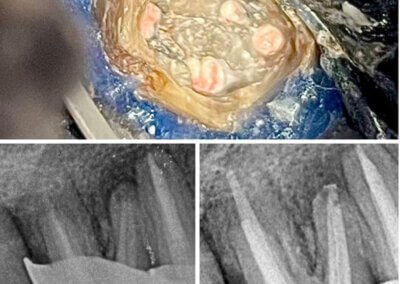

Reconstituirea coronară cu materiale de calitate conferă rezistență pe termen lung.

Tratamentele corecte reduc riscul de infecții și complicații viitoare.